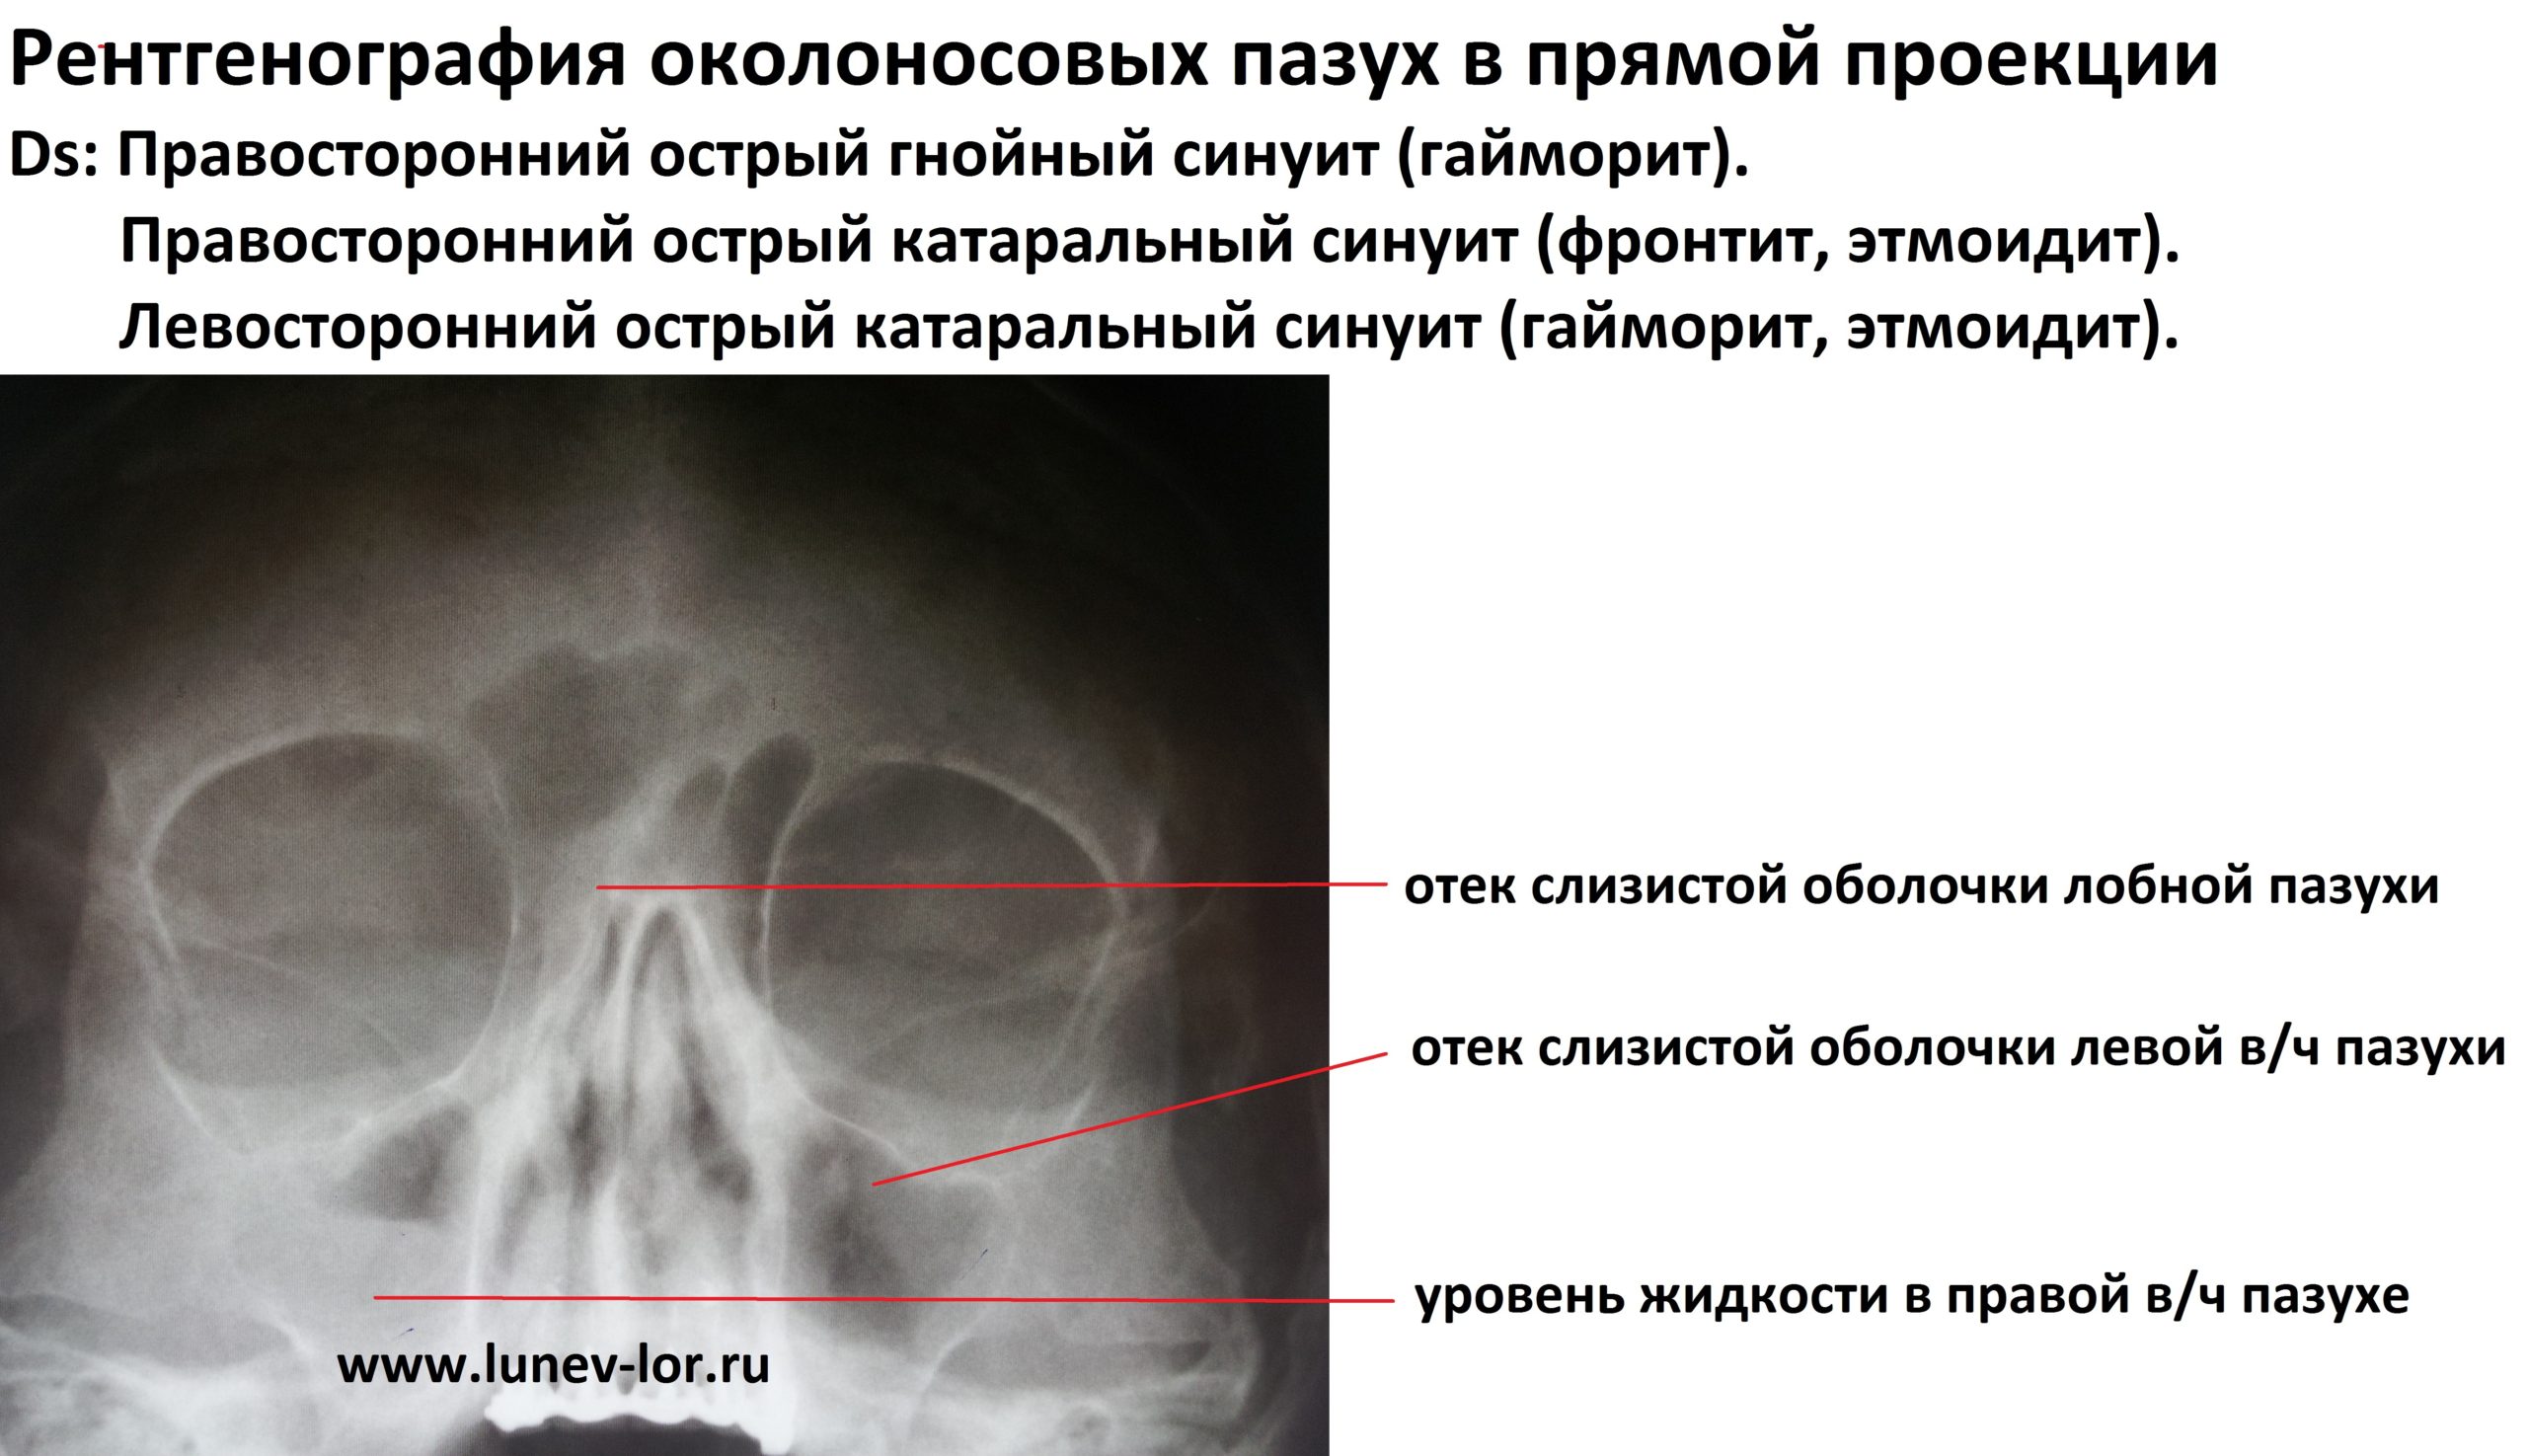

КТ-снимки хронического этмоидита: подробная визуализация